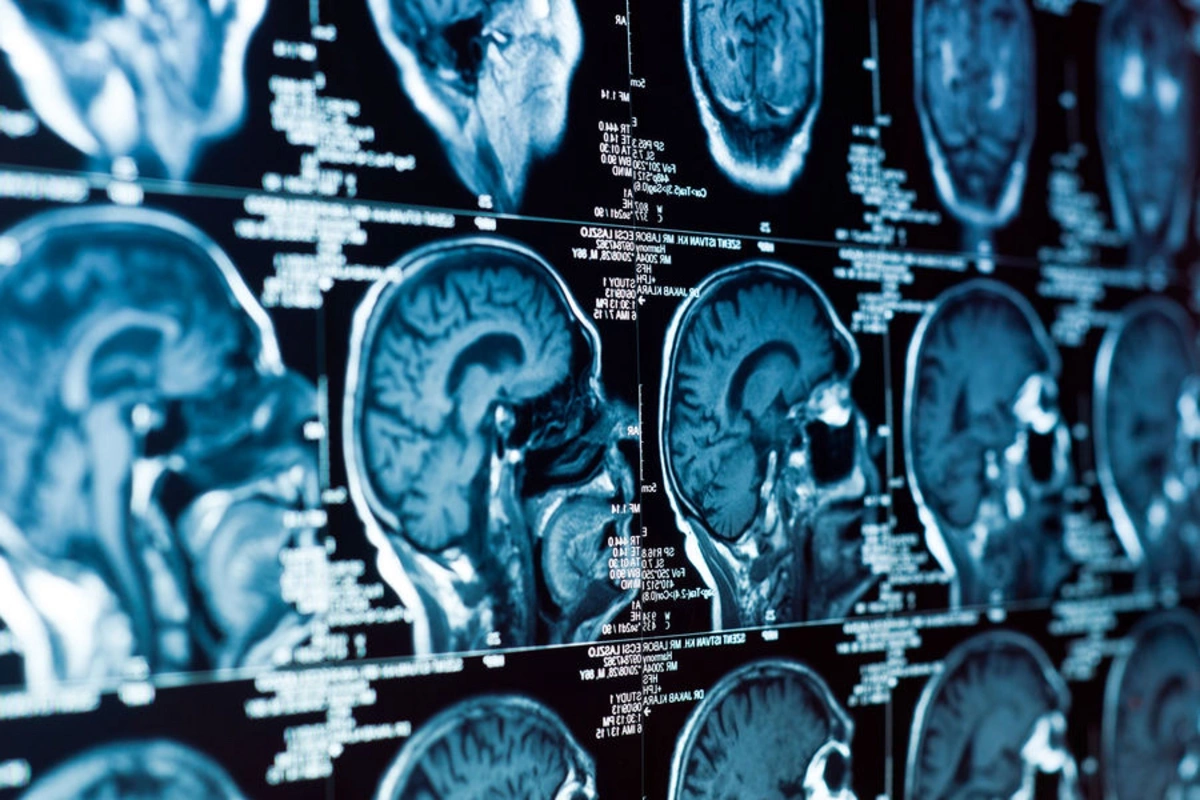

Beyində demensiyanın gözlənilməz səbəbi tapıldı

Mərkəzi sinir sisteminin köməkçi hüceyrələri olan astrotsitlərdə yaranan molekullar demensiyanın inkişafında əsas rol oynaya bilər.

Tədqiqatçılar diqqəti mitoxondrilərə yönəldiblər - bunlar hüceyrədə enerji istehsalına və aktiv oksigen formalarının (AOF) yaranmasına cavabdeh orqanoidləri təşkil edir. Normal şəraitdə az miqdarda AOF beynin fəaliyyətini dəstəkləyir, lakin onların həddindən artıq toplanması hüceyrə strukturlarına zərər vurur.

Alimlər müəyyən ediblər ki, artıq miqdarda AOF neyronların deyil, məhz astrotsitlərin mitoxondrilərində əmələ gəlir.

Bu hüceyrələr sinir hüceyrələri ilə sıx əlaqədə olduqları üçün, bu proses iltihabın yaranmasına və neyronların zədələnməsinə səbəb olur.